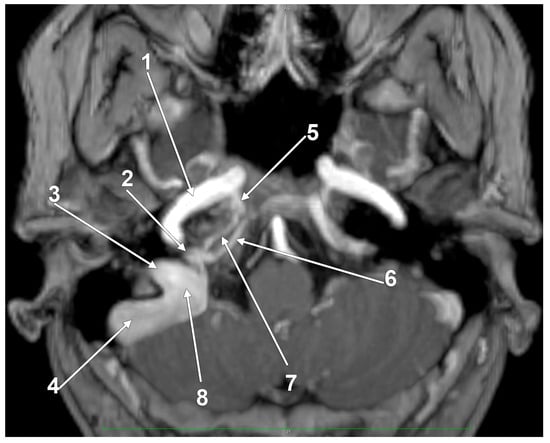

The “Condylar Jugular Diverticulum”: True or False?